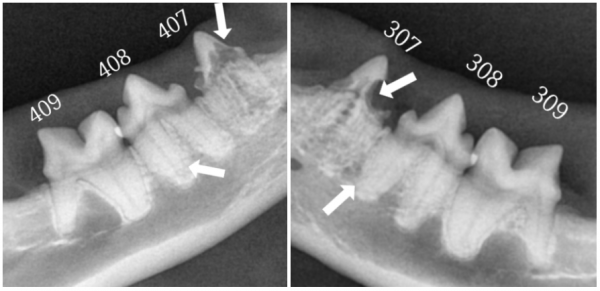

407,408 치아흡수성병변

307,308 치아흡수성병변